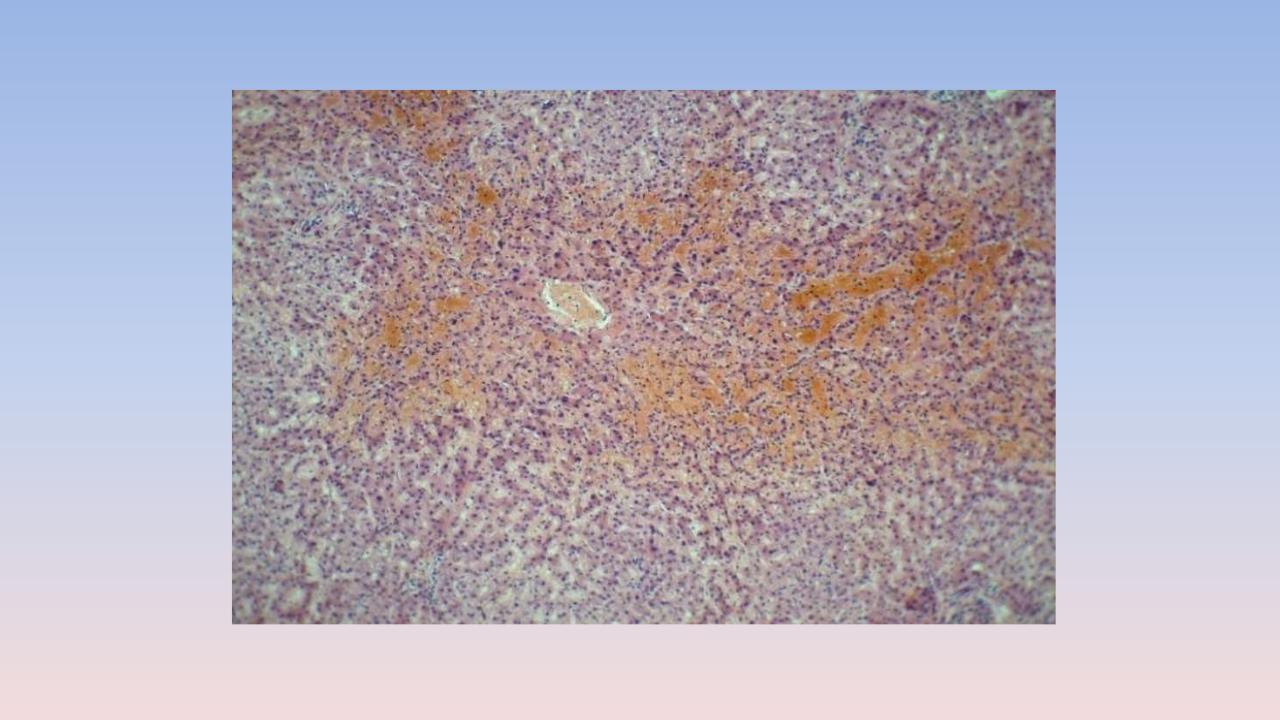

4. Мускатная печень